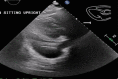

Key clinical message: The occurrence of a large pericardial effusion is not a commonly noted adverse event associated with pembrolizumab and our report demonstrates that a rapid development can be diagnosed with close monitoring and triage to acute medical settings.

Abstract: Pembrolizumab is an immune checkpoint inhibitor used in various types of cancers. Pericardial tamponade is a rare side effect reported in only very few case reports. Early recognition and therapeutic intervention is vital in all cases. We report a case of a 54-year-old male with Stage 3 lung adenocarcinoma who developed cardiac tamponade secondary to pembrolizumab and subsequently required pericardial window.